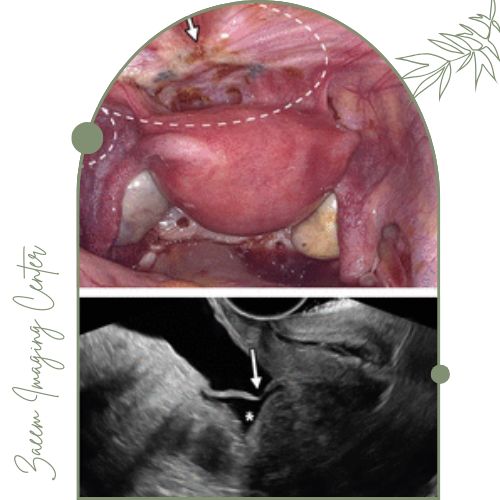

سونوگرافی اندومتریوز

سونوگرافی اندومتریوز یکی از روشهای تصویربرداری تخصصی برای تشخیص و ارزیابی ضایعات اندومتریوز در بدن بانوان است. اندومتریوز بیماری نسبتا شایعی است که طی آن بافت مخاط رحم (اندومتر) خارج از رحم رشد میکند و میتواند علائم دردناک و مشکلات باروری ایجاد کند. سونوگرافی ترانس واژینال یا شکمی با استفاده از امواج صوتی تصاویری دقیق از اندامهای لگن، رحم، تخمدان و سایر بافتهای اطراف ارائه میدهد و به پزشک امکان شناسایی ضایعات، کیستهای اندومتریوز و چسبندگیها را به صورت غیرتهاجمی میدهد. این روش معمولاً درد یا خطر خاصی ندارد و یکی از ابزارهای موثر در بررسی اولیه و پیگیری وضعیت بیماری در خانمها محسوب میشود.